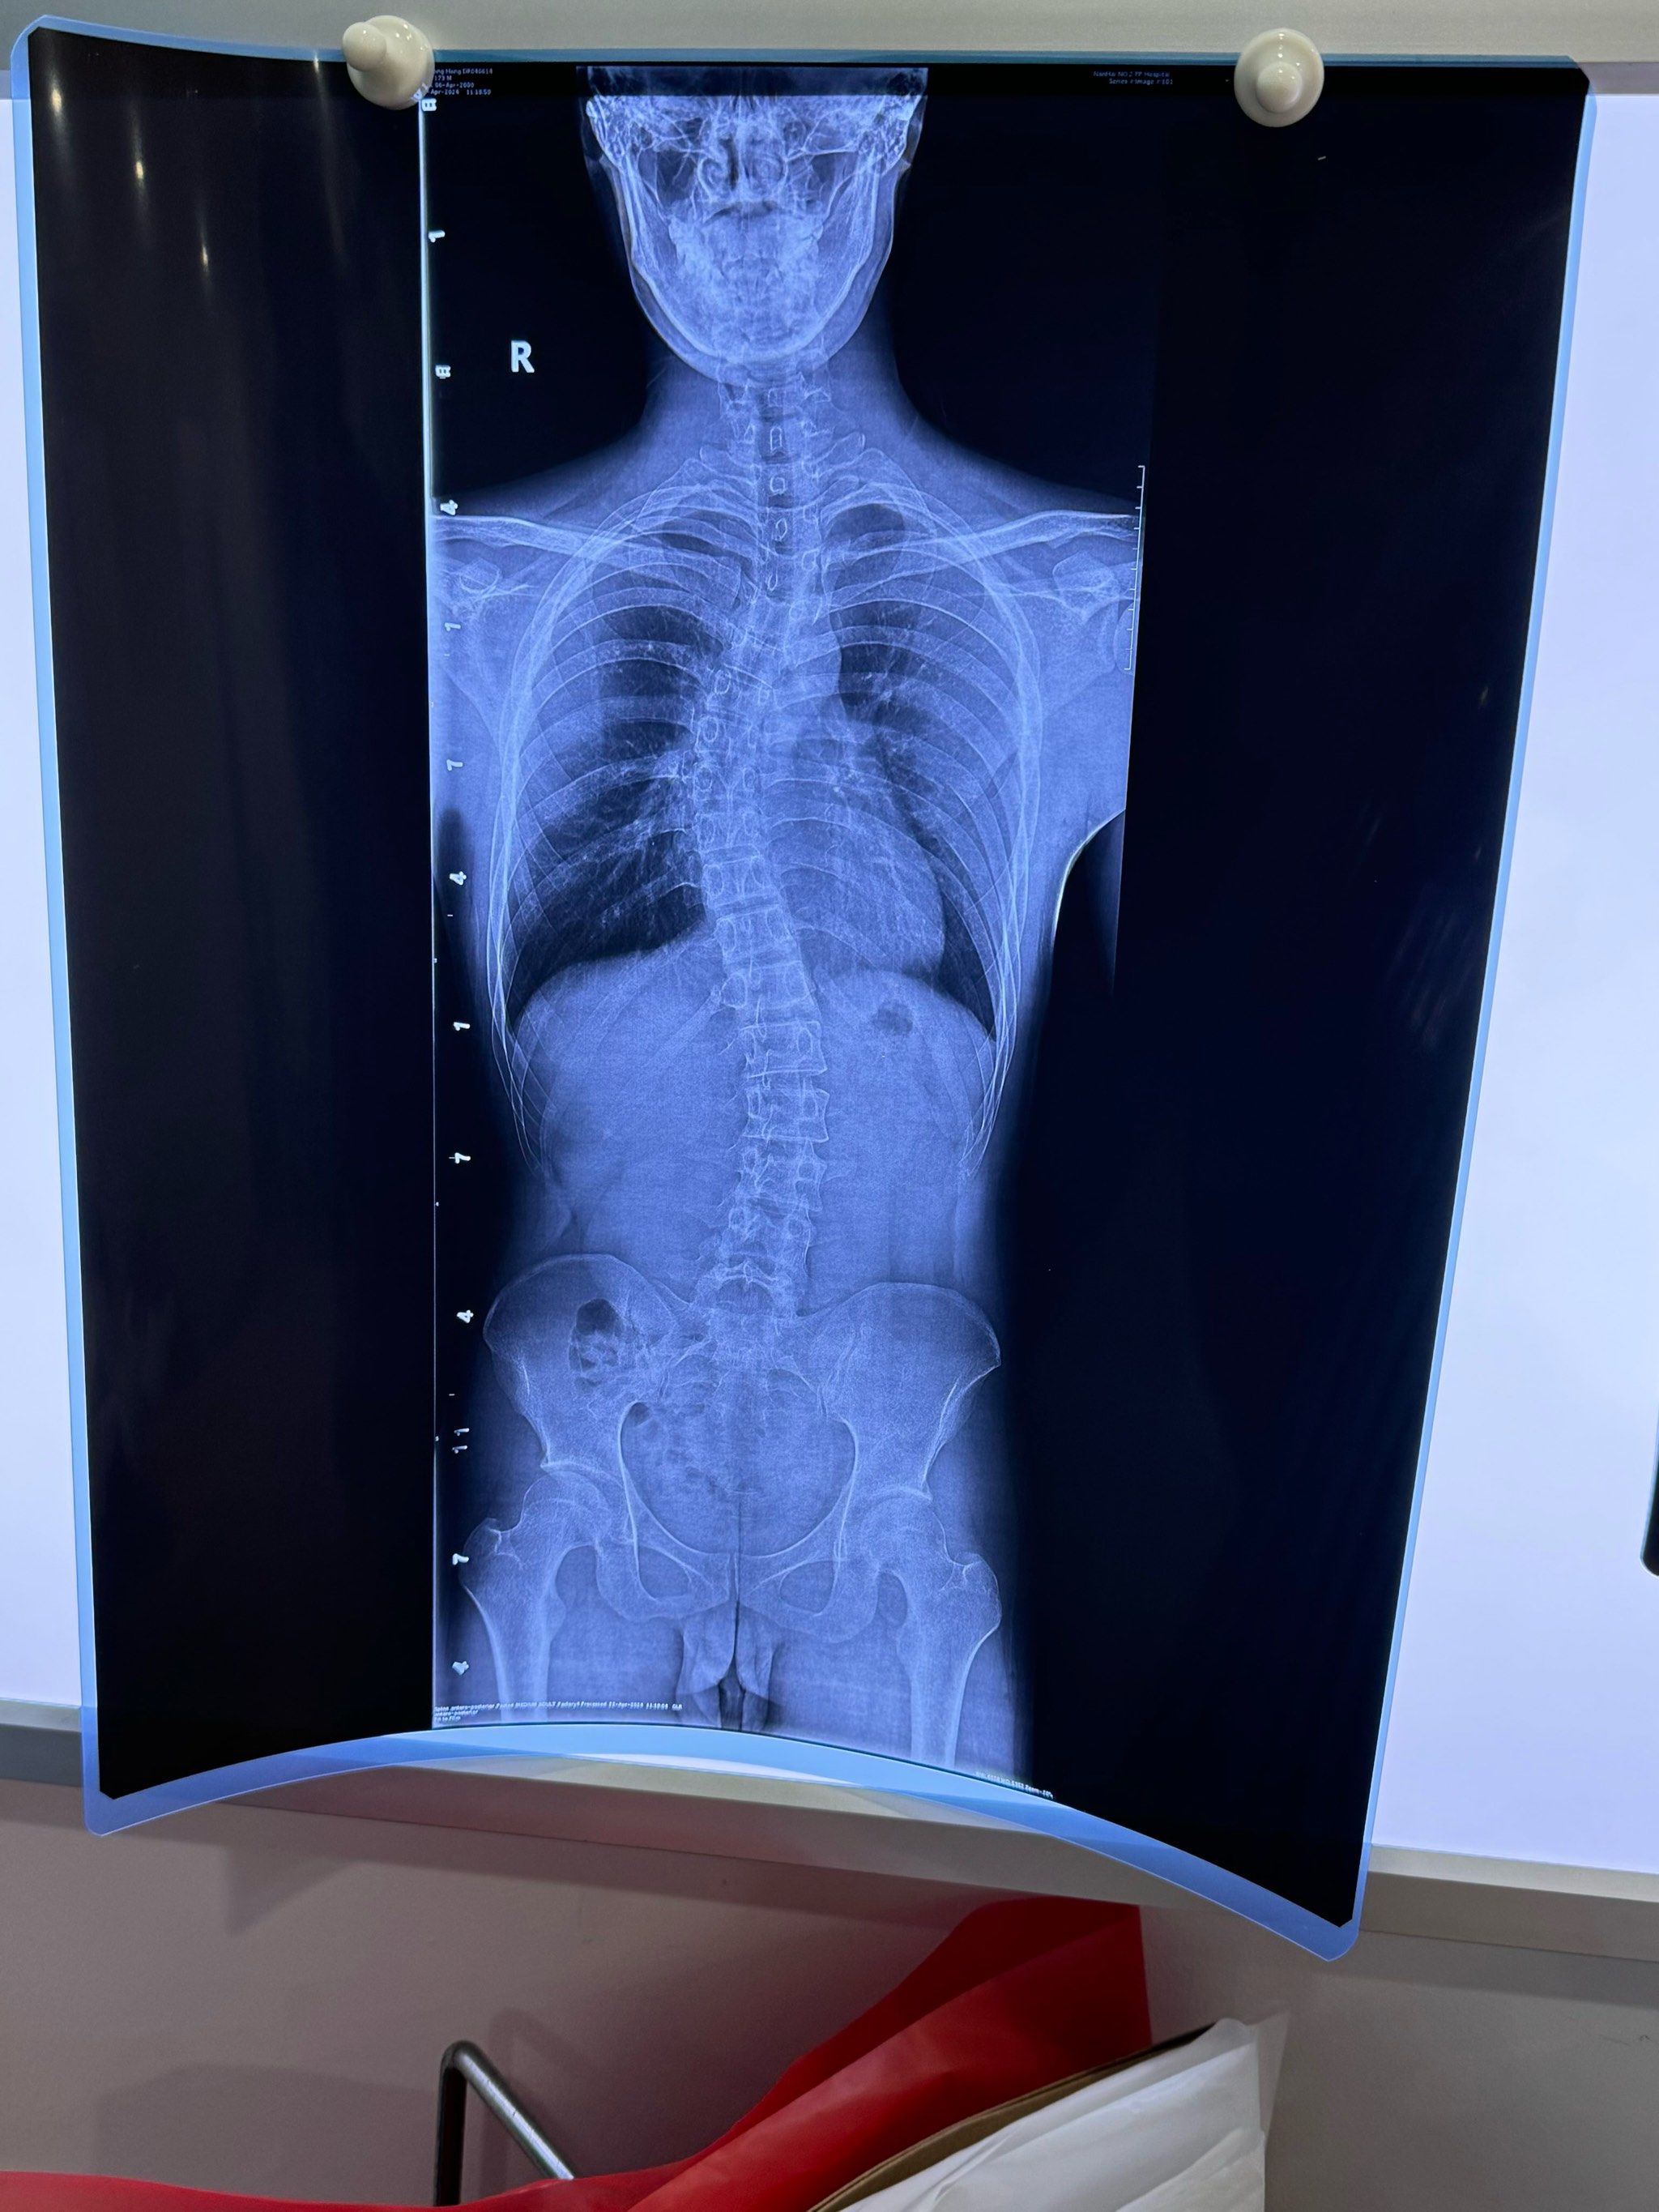

分享一个重度脊柱侧弯导致体态畸形的案例

21岁男孩脊柱侧弯高达60度,胸椎段侧弯最重,患者胸椎明显向右侧弯